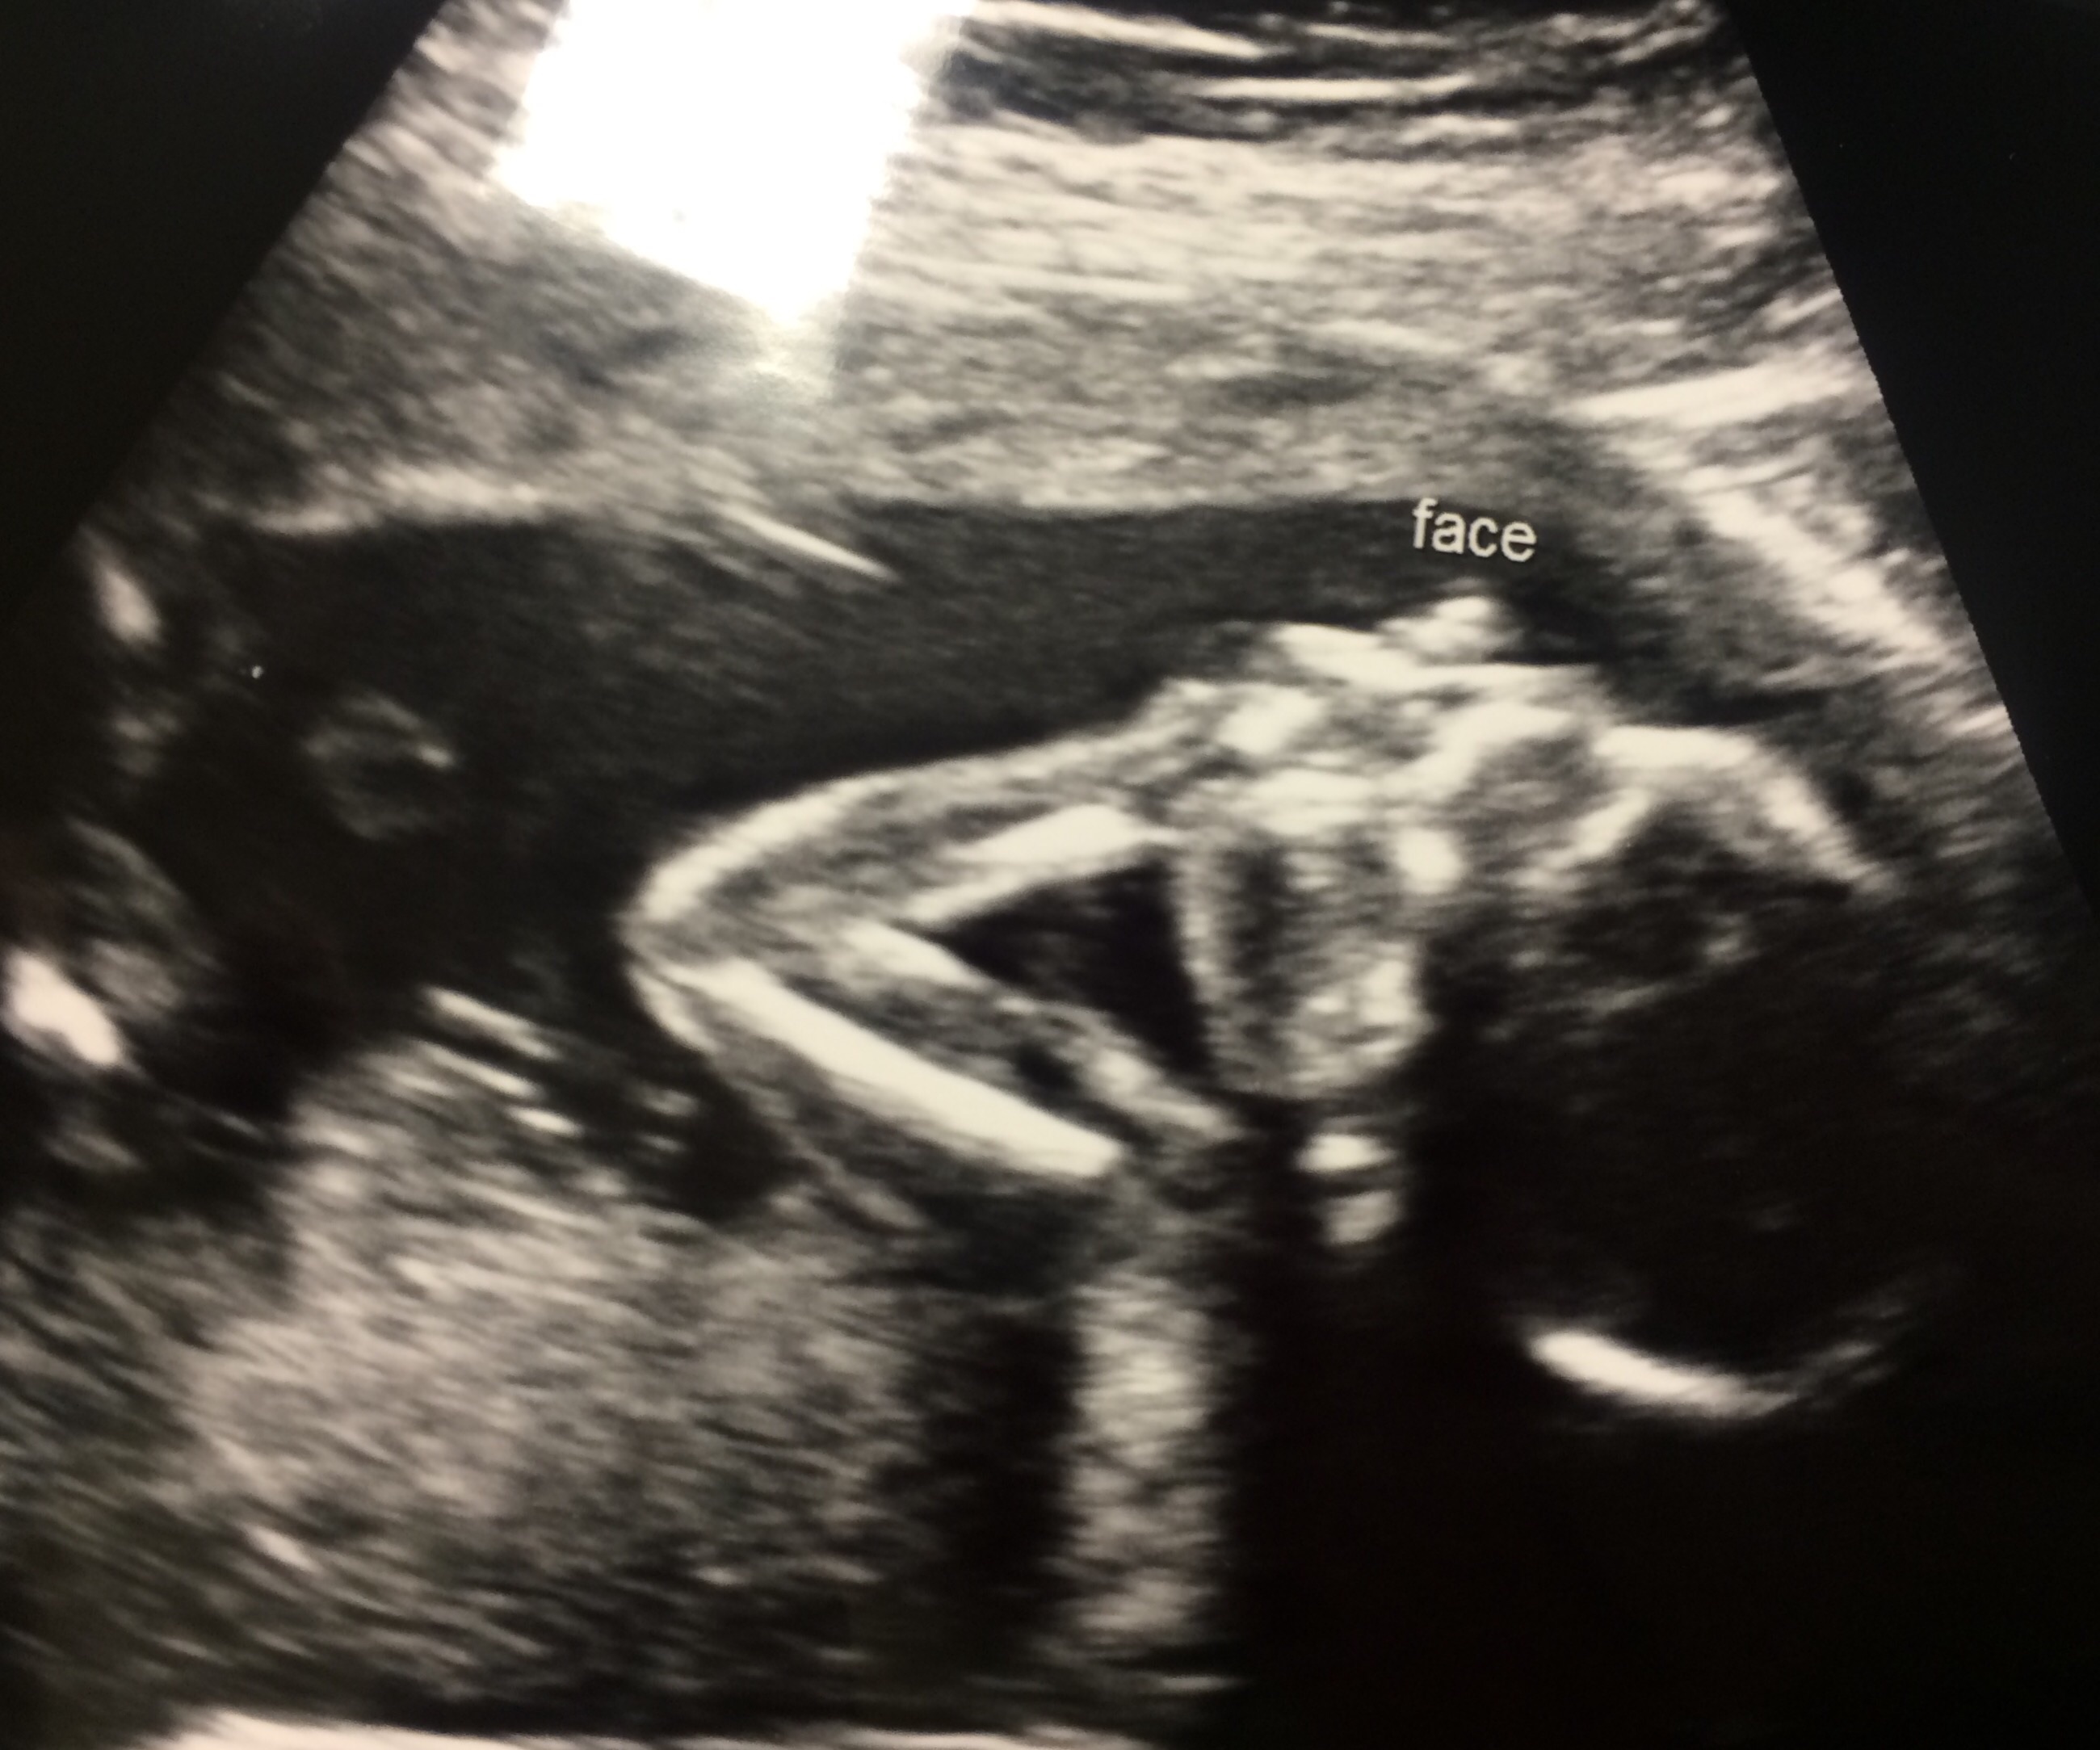

FTM! Just found out tonight we are expecting a little girl!! We are thrilled! We are deciding between Vienna and Mila, help? We need middle names too! Due Oct. 20